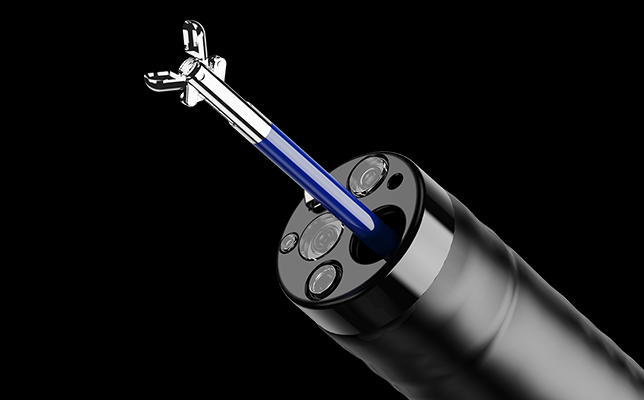

Эластичный изгибВо время эндоскопических процедур он может адаптироваться к различным изгибам толстой кишки. Способен саморегулироваться и поворачивать корпус эндоскопа к просвету в таких областях, как изгиб селезенки и печеночный изгиб, что уменьшает необходимость манипуляций с эндоскопом и повышает комфорт пациента. Инструмент размером 4,2 мм3,2 мм для гастроскопа / 4,2 мм для колоноскопа. Облегчает выбор расходных материалов и обеспивает достаточную мощность всасывания

Инструмент размером 4,2 мм3,2 мм для гастроскопа / 4,2 мм для колоноскопа. Облегчает выбор расходных материалов и обеспивает достаточную мощность всасывания Обзор на 170°Новый колоноскоп серии 50 имеет область обзора 170°, что расширяет диапазон обследования, уменьшает количество слепых зон и, тем самым, снижает частоту ошибочной диагностики кишечных заболеваний.

Инструментальный канал 3,7 мм. Эндоскопы системы AQ-200 оснащаются инструментальными каналами диаметром 3,7мм для колоноскопов и 2,8мм — для гастроскопов, что обеспечивает:

- высокую эффективность аспирации и промывания,

- возможность использования широкого спектра эндохирургических инструментов,

- комфортную работу с расходными материалами и аксессуарами.

Угол обзора 170°. Оптика с углом обзора 170° даёт расширенное поле зрения, позволяя врачу охватить больше анатомических структур в одном кадре. Это снижает вероятность пропуска патологических участков и уменьшает количество "слепых зон", что особенно важно при скрининговых процедурах и прицельных биопсиях.